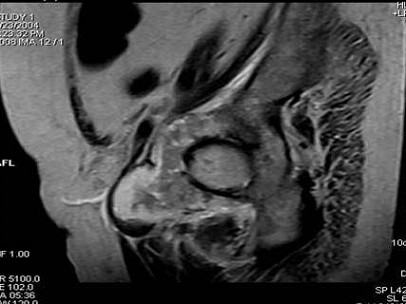

[单选题]患者,男,38岁,左髋部疼痛,并逐渐加重,体检:左髋部明显肿胀压痛,无明显发热,结合所提供的图片,最可能的诊断是()A .骨巨细胞瘤B .纤维肉瘤C .骨肉瘤D .软骨肉瘤E .软骨黏液纤维瘤

[单选题]患者,男,38岁,左髋部疼痛,并逐渐加重,体检:左髋部明显肿胀压痛,无明显发热,结合所提供的图片,最可能的诊断是()A . 骨巨细胞瘤B . 纤维肉瘤C . 骨肉瘤D . 软骨肉瘤E . 软骨黏液纤维瘤